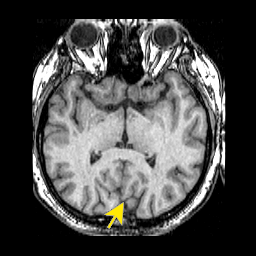

067parieto occipital.png